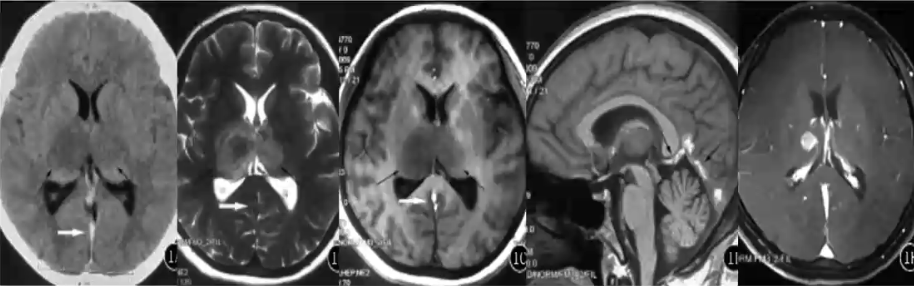

大脑大静脉血栓

❖ Galen静脉血栓形成时,相应引流区常同时受累,且部位、范围基本对称

❖ 典型影像学表现:直接征象为CT上Galen静脉内的高密度影,MR上Galen静脉内的短T1、长T2信号。间接征象为CT上的双侧丘脑、内囊及基底节区对称性低密度影,MR上的受累区对称性的长T1、长T2异常信号;可继发出血性脑梗塞